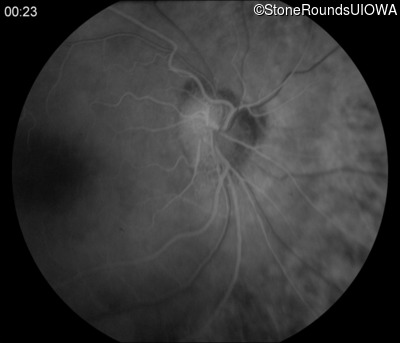

Fluorescein Angiography - Right - 20/50 +2

Exemplar

Fluorescein Angiography - Left - 20/160